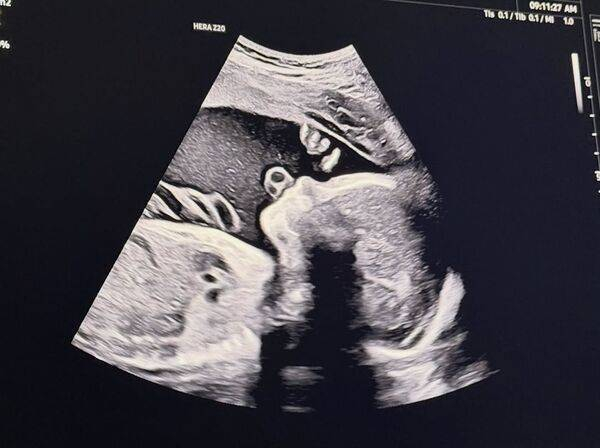

前FTISLAND成员宋承炫近年淡出演艺圈后,人生迎来全新阶段。21日他在社群平台分享了两张超音波照片,并写下“就快见面了,我们的小太阳”,疑似公开即将升格当爸爸的喜讯,消息一出立刻引发关注。

宋承炫在2024年与圈外女友结婚并移居美国生活。从他曝光的照片中可以看到,一张为黑白超音波影像,另一张则为3D立体超音波,能清楚看到宝宝的脸部轮廓与姿态,画面温馨又充满期待,也让粉丝纷纷留言祝福。